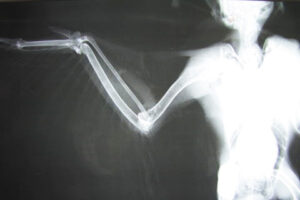

受傷後それほど時間が経っていないらしく、生々しい血しぶきが翼の裏を真っ赤に染めています。皮膚は裂け、むき出しになった筋肉や腱は所々で切断されています。さらにレントゲン検査では肘と肩の部分に脱臼が認められました。

収容された時の状況や怪我の具合から、この若いハヤブサは交通事故に遭ったと思われました。 血液検査などで手術に耐えられると判断されたため、輸液と全身麻酔を施しながら、裂傷と脱臼の整復を行いました。